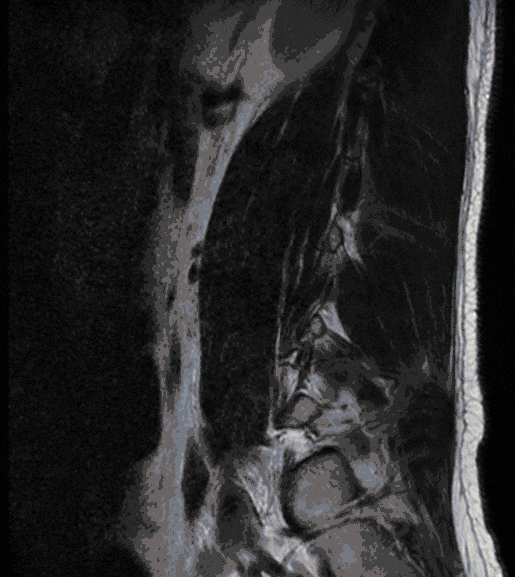

Gelenkzysten treten meist in Folge einer degenerativen Erkrankung der Wirbelgelenke (Facetten-Gelenke) auf und können Ausdruck einer Instabilität sein. Da Gelenkzysten zu einer deutlichen Einengung des Wirbelkanals führen können, können sie mit Beschwerden einhergehen, die einer Spinalkanalstenose gleichen.

Bei entsprechenden Beschwerden und Versagen konservativer Therapie bzw. Auftreten von neurologischen Defiziten kann eine operative Resektion erfolgen.